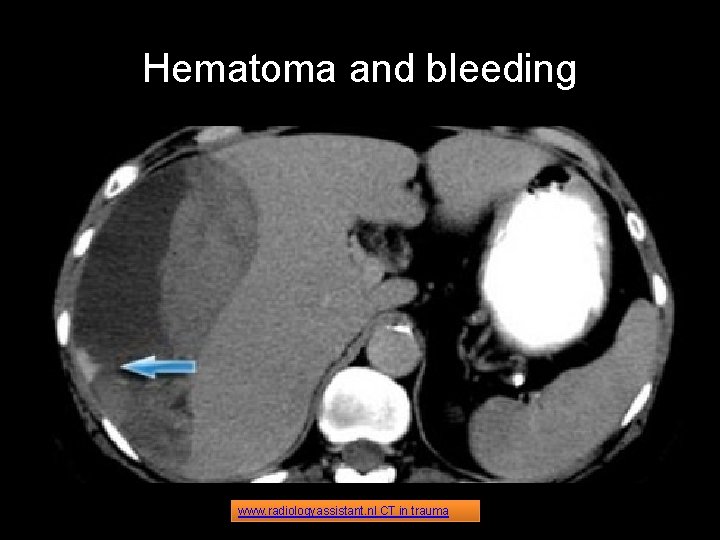

ABDOMINAL TC Abdominal trauma is responsible for 10%. The findings to look for in abdominal trauma are the following: • • Hemoperitoneum Contrast blush consistent with active extravasation Laceration: Linear shaped hypodense areas Hematomas: oval or round shaped areas Contusions: vague ill-defined hypodense areas that are less well perfused Pneumoperitoneum Devascularization of organs or parts of organs Nowadays there is a trend towards non-operative management of blunt abdominal trauma. More than 50% of splenic injury, 80% of liver injury and virtually all renal injurys are managed non-operatively, because patients proved to have better outcomes on the long term related to visceral salvage. www. radiologyassistant. nl CT in trauma

Hematoma and bleeding www. radiologyassistant. nl CT in trauma